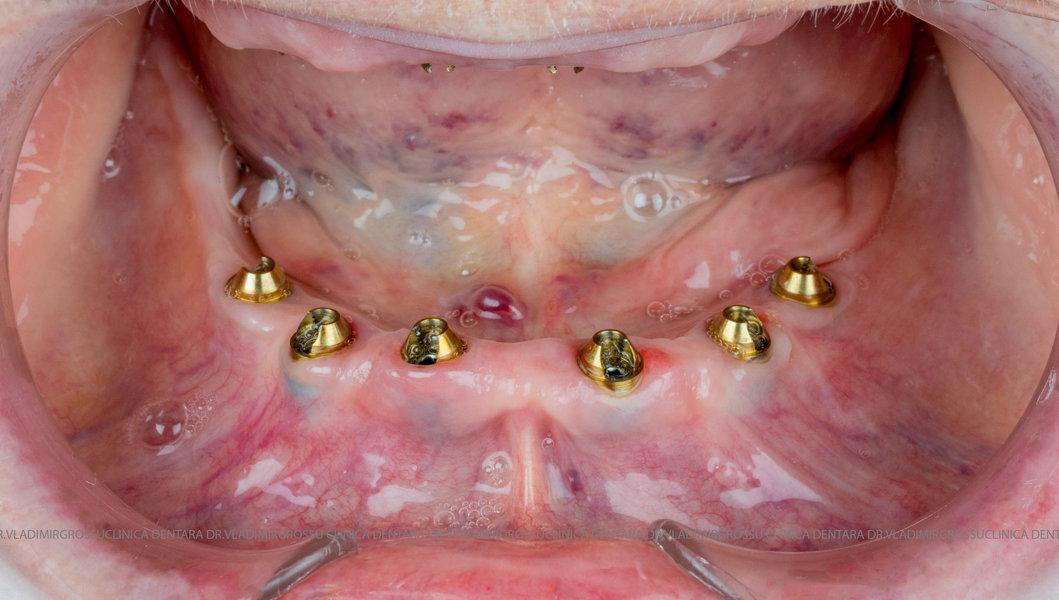

Cazuri clinice conceptul All-on-6